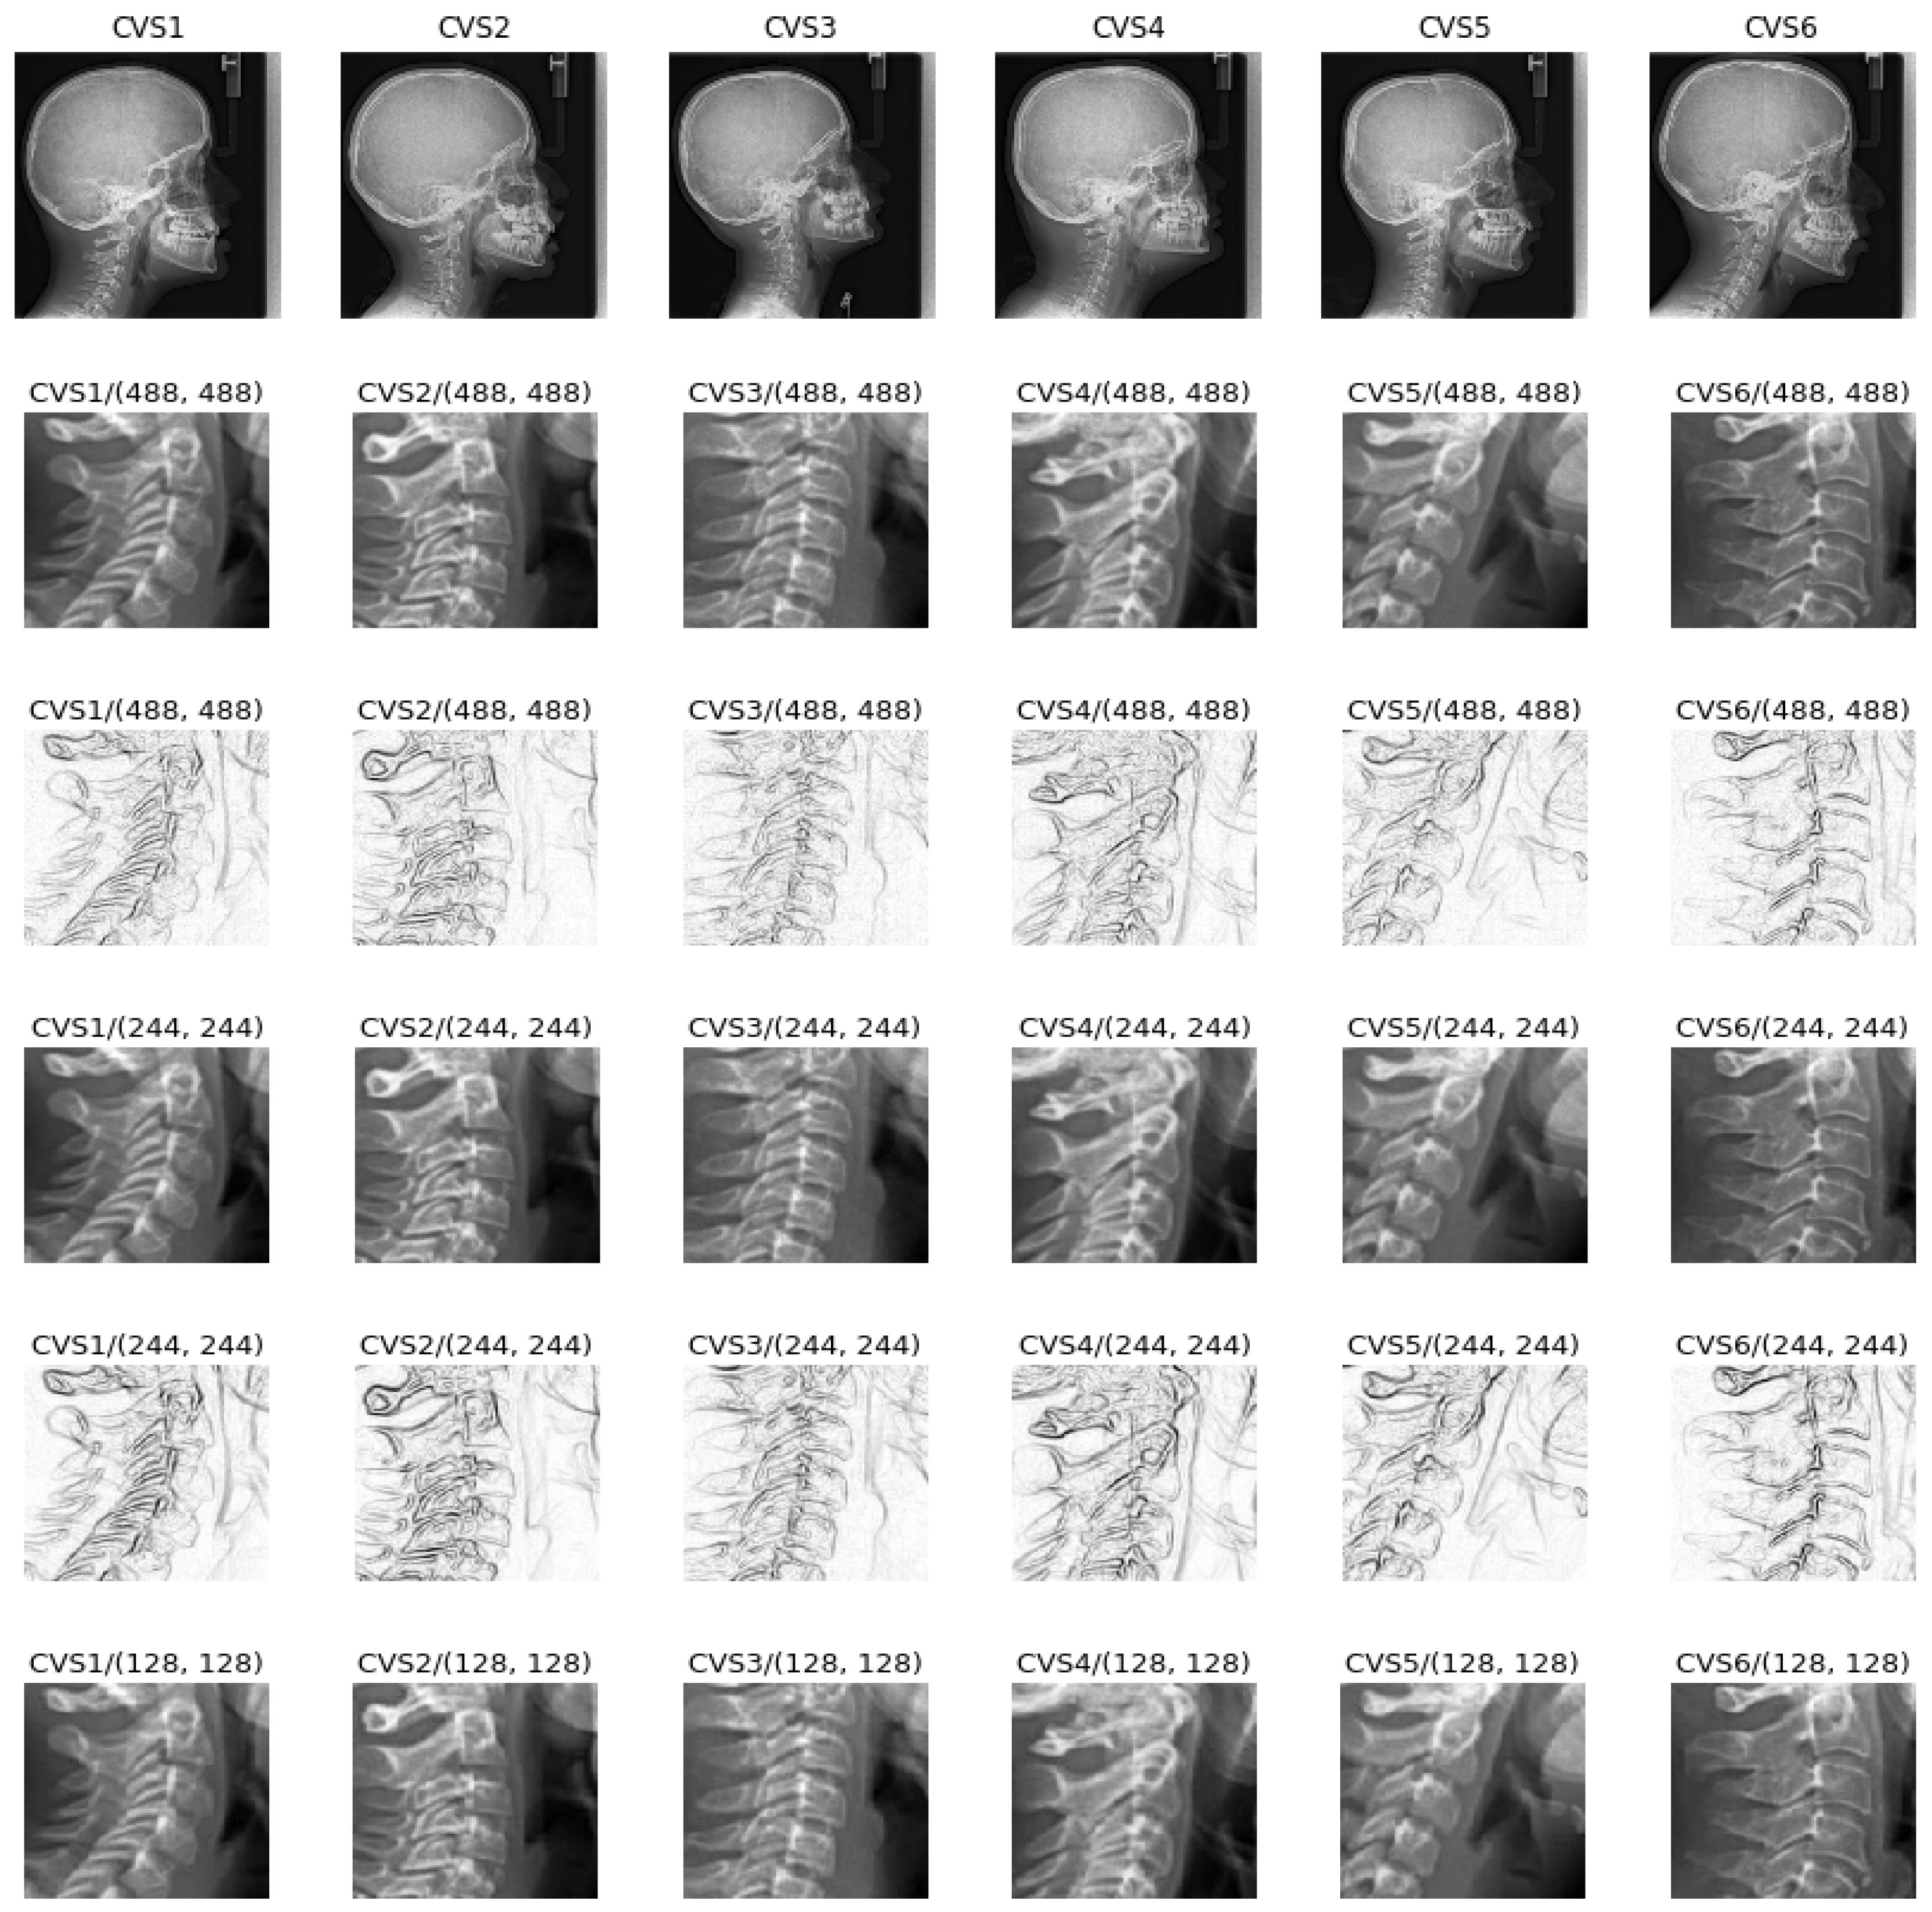

:1. Introduction

- Cervical stage 1 (CS1) = 2 years before mandibular growth peak:Lower borders of C2 to C4 vertebrae are flat. C3 and C4 superior borders are tapered from posterior to anterior.

- Cervical stage 2 (CS2) = 1 year before mandibular growth peak:Lower border of C2 presents a concavity. Bodies of C3 and C4 are the same.

- Cervical stage 3 (CS3) = during the year of the mandibular growth peak:Lower borders of C2 and C3 present concavities. Vertebrae are growing so C3 and C4 may be either trapezoid or rectangular shape, as superior borders are less and less tapered.

- Cervical stage 4 (CS4) = 1 or 2 years after mandibular growth peak:Lower borders of C2, C3 and C4 present concavities. Both C3 and C4 bodies are rectangular with horizontal superior borders longer than higher.

- Cervical stage 5 (CS5) = 1 year after the end of mandibular growth peak:Still concavities of lower borders of C2, C3 and C4. At least one of C3 or C4 bodies are squared and spaces between bodies are reduced.

- Cervical stage 6 (CS6) = 2 years after the end of mandibular growth peak:The concavities of lower borders of C2 to C4 have deepened. C3 and C4 bodies are both square or rectangular vertical in shape (bodies higher than wide).

2. Preprocessing of the Data